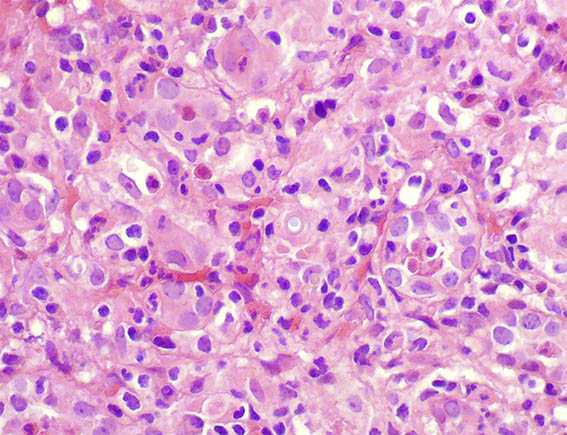

Bilateral renal biopsies were performed.See the images.

Figure 3. H&E, X400.